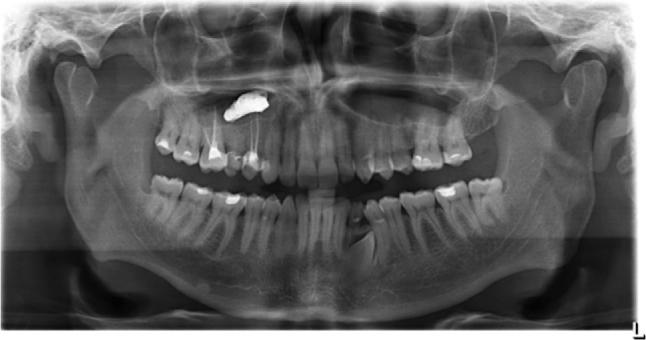

Foreign bodies found in the maxillary sinus include tooth roots, burs, dental impression material, root-filling materials, dental implants, and needles. The purpose of this paper was to present an unusual case of a large foreign body of endodontic origin (root-filling material) removed from the maxillary sinus. A 45-year-old generally healthy male patient reported to the Department of Conservative Dentistry with Endodontics of the Medical University of Silesia, because of orbital and buccal pain on the right side of his face and headaches in the preceding 6 months. Those symptoms were associated with the end of endodontic treatment of teeth 14 and 16. Periapical X-rays, including of teeth 14 and 16, showed the presence of root canal filling with extrusion of endodontic obturation material beyond the apices of tooth 14. In the case of tooth 16, a completely filled palatal canal and incompletely filled buccal canals were found. There was also an irregular dimness at the upper edge of the X-ray image. Panoramic radiography and computed tomography demonstrated a foreign body in the right sinus. Sinus exploration was performed via a surgical procedure conducted using topical anesthesia. The root apices of tooth 14 were resected, and foreign substance was removed. The practitioner did not correctly recognize a complication that occurred during endodontic treatment, which resulted in extrusion of endodontic material beyond the root apices of tooth 14. This case emphasizes the potential impact that an involved maxillary sinus may have on endodontic therapy. Detailed diagnostic identification based on the medical interview, physical and histopathological examinations, and diagnostic imaging allowed rapid surgical intervention and prevented local and general complications. It is important to realize that the range of the periapical X-ray projection is not always sufficient.

在上颌窦中发现的异物包括牙根、牙钻、牙科印模材料、根管充填材料、牙种植体和针头。本文的目的是介绍一例罕见的源自牙髓治疗的大型异物(根管充填材料)从上颌窦取出的病例。一名45岁的健康男性患者因右侧面部眼眶和颊部疼痛以及前6个月的头痛,前往西里西亚医科大学保守牙科与牙髓病科就诊。这些症状与14号和16号牙齿的牙髓治疗结束有关。包括14号和16号牙齿在内的根尖X线片显示根管充填,牙髓充填材料超出了14号牙齿根尖。对于16号牙齿,发现腭根管完全充填,颊根管充填不完全。X线图像上缘还存在不规则的模糊影。全景X线摄影和计算机断层扫描显示右侧上颌窦有异物。通过局部麻醉下的外科手术进行鼻窦探查。切除了14号牙齿的根尖,并取出了异物。该从业者未正确识别牙髓治疗期间发生的并发症,导致牙髓材料超出14号牙齿根尖。该病例强调了受累上颌窦可能对牙髓治疗产生的潜在影响。基于医学问诊、体格检查、组织病理学检查和诊断成像进行详细的诊断识别,有助于快速进行手术干预并预防局部和全身并发症。必须认识到根尖X线投影范围并不总是足够的。